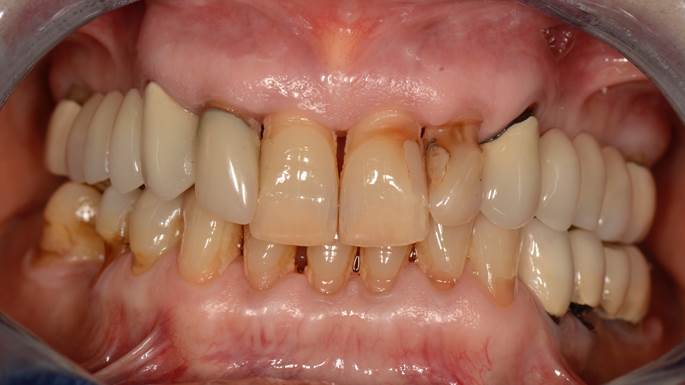

“AnyRidge shows excellent initial stability

& stable results after immediate loading in

upper fully edentulous case. ”

Clinical case: Extraction of all teeth in upper maxilla,

immediate implant placement, & provisionalization

- Courtesy of Dr. Iulian Filipov, Romania -